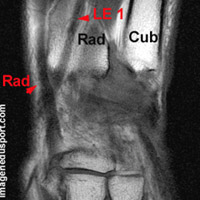

Le Muscle Long Extenseur du I (M Extensor Pollicis longus) situé sous le court extenseur du pouce, il s'insère sur la face postérieure de l'ulna et sur la partie attenante de la membrane inter-osseuse.

Son corps musculaire, se dirige en bas et en dehors, glissant à la face postérieure du radius.

Terminaison : le tendon glisse dans la gouttière moyenne de la face postérieure de l'épiphyse du radius. Il est situé en général en regard du tubercule de Lister ou sur son versant ulnaire. Il sur-croise les radiaux à hauteur de la première rangée du carpe et forme la limite externe et postérieure de la tabatière anatomique.